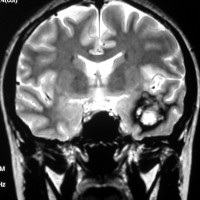

左上のT2*でみられるように多発性海綿状血管腫の成人男性に発生した中脳海綿状血管腫です。複視と歩行失調で発症して,数回の脳幹部出血を繰り返し,水頭症になったために第3脳室開窓術がなされました。それでも出血は止まらず、両側の動眼神経麻痺による両側眼瞼下垂,歩行失調,嚥下障害などさまざまな中脳症状が進行しました。

しかたがないので手術で摘出しました。なんとか眼瞼が持ち上がるようになり歩行も可能で嚥下もできます。幸いだったのは感覚路(脊髄視床路)の障害による体性疼痛が生じなかったことです。

手術は経テント法 OTA という手法でした(クリックと手技が書いてあります)

片方の下丘の損傷だけでは神経脱落症状が出ないので,中脳内部の腫瘍を摘出するには下丘という狭い場所を切開して入りますが,この患者さんは左上丘も出血のために破壊されていて,間口が広かったといえます。でもこの手術は難しすぎるので決して積極的にはしません。